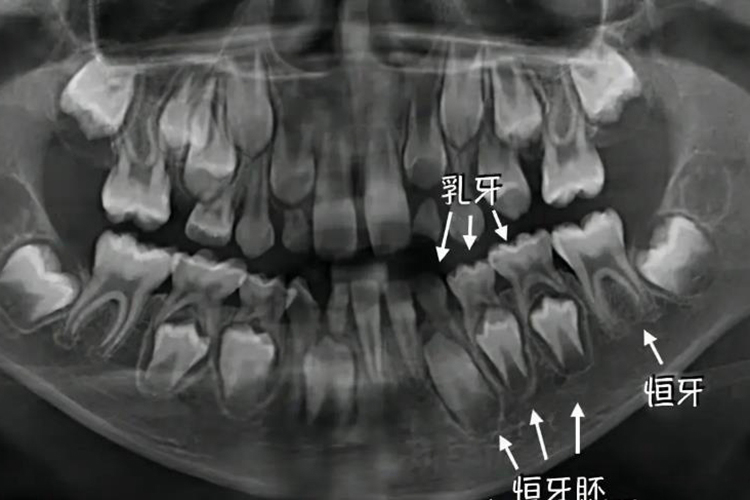

牙胚是牙板最末端细胞增生发育而形成,是牙齿发育的最开始阶段。

牙胚是牙板最末端细胞增生发育而形成,由成釉器、牙乳头和牙囊三个部分组成。牙胚的形成可分为蕾状期、帽状期和钟状期,不同阶段形态不同。

牙胚是牙板最末端细胞增生发育而形成,由成釉器、牙乳头和牙囊三个部分组成。成釉器起源于口腔外胚层,形成釉质。牙乳头起源于外胚间叶组织,形成牙髓和牙本质。牙囊起源于外胚间叶组织,形成牙骨质、牙周膜和固有牙槽骨,牙胚的发生是口腔外胚层和外胚间叶组织互相作用的结果。